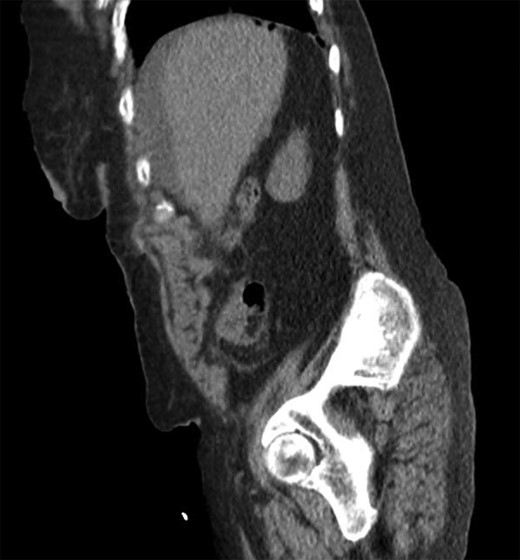

She was a former smoker with past medical history of hypertension, cerebrovascular event, hypothyroidism, and hyperlipidemia, and esophagogastroduodenoscopy and colonoscopy for gastrointestinal bleed, without past surgical history. On physical exam, she was normothermic, tachycardic, hypotensive and saturating 100% on room air. She had a distended, diffusely tender abdomen with guarding and rebound tenderness. Laboratory results were notable for leukocytosis with a left shift, chronic anemia, and acute kidney injury. Computed tomography of the chest, abdomen, and pelvis showed esophageal thickening, free air under the diaphragm, duodenal inflammation, generalized mesenteric fat stranding, free fluid in the abdomen and pelvis, and a thickened and inflamed bladder wall with irregular foci of hyperintensity within the bladder lumen and a left hydroureteronephrosis (Figs 1–3).

Coronal computed tomography showing a thickened inflamed bladder wall and irregular foci of hyperintensity within the bladder lumen.